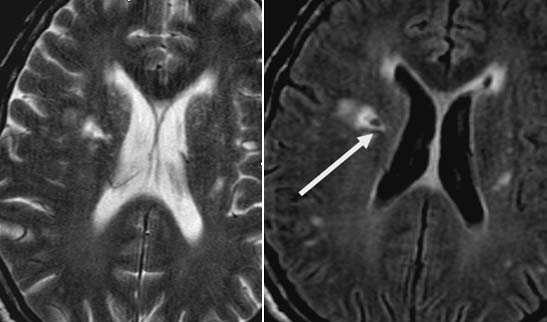

Внутримозговая гематома, поздний подострый период (14-21 день) с перифокальным отеком вокруг гематомы.

Внутримозговая гематома правой теменной доли. Граница поздней подострой и ранней хронической стадии. В Т2-ВИ виден ободок гемосидерина (стрелка).

Хочется подчеркнуть возможность МРТ в выявлении последствий геморрагического поражения - остается хорошо дифференцируемый по Т2 ободок гемосидерина, недоступный для визуализации при других методах нейровизуализации.

Стрелками показан ободок гемосидерина по периферии постишемической кисты.